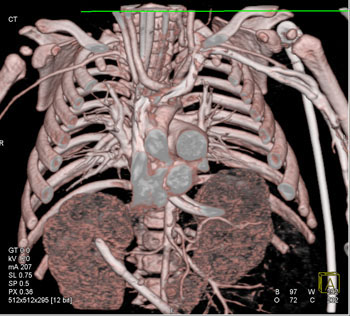

Question 8: Infant with chest and abdominal wall defect. What is the diagnosis?

Diagnosis: Pentalogy of Cantrell

• Exteriorization of the heart

• Associated with CV malformations like ASD (50%), VSD (18%) and TOF (11%)

• Omphalocele and defect lower sternum

• Deficiency of diaphragmatic pericardium

• Prognosis: death within first month of life